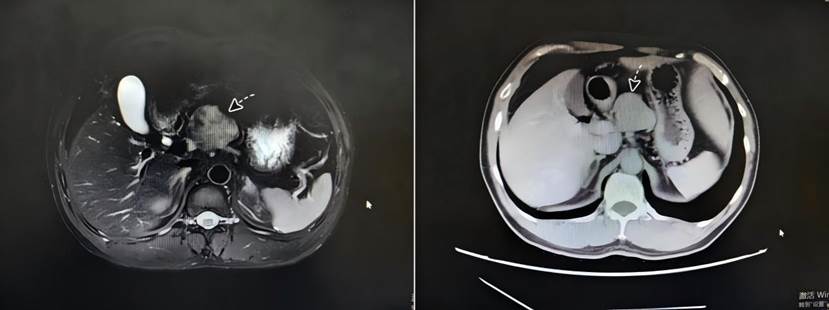

患者有着20多年乙肝病史,在一次复查中意外发现肝脏存在占位性病变。进一步检查确认,肿瘤位于肝脏深处的尾状叶。这一区域解剖结构复杂、空间狭小,且被肝脏主要血管系统紧密包绕,手术视野暴露极差,被视为“肝脏外科最后的禁区”。面对病情,患者及家属焦虑万分:如果选择传统开腹手术,创伤大、恢复难;而若放任不管,肿瘤随时可能恶化,危及生命。

面对这一棘手病例,南华医院肝胆外科李卫主任医师及团队经过详尽的术前评估与讨论,决定采用先进的腹腔镜微创技术为患者解除病痛。李卫介绍:“传统开腹手术对于这类患者来说,无异于一场‘浩劫’。而腹腔镜技术就像把医生的‘眼睛’和‘器械’通过钥匙孔般的通道送入体内,在高清放大的视野下,我们可以清晰地分辨血管和肿瘤的边界,实现毫米级的精细操作。”相较于传统手术,腹腔镜肝尾状叶切除术具有创伤小、出血少、恢复快、并发症少等显著优势。

手术过程中,李卫带领团队在狭小的空间内灵活操作,如同绣花般精细地游离、钳夹、凝闭、离断血管,成功将肿瘤从紧贴的下腔静脉旁完整剥离,整个过程出血量极少,未输血,手术圆满成功。这一高难度手术的完成,不仅体现了团队深厚的解剖学知识积累和成熟的腹腔镜操作技巧,更彰显了南华医院肝胆外科在处理复杂、疑难肝脏疾病方面的强大能力。